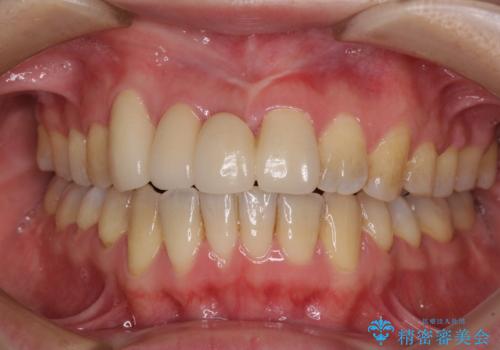

補助装置により上顎歯列を遠心移動させたため、非抜歯でしたが口元の突出感をある程度改善させることができました。

欠けてしまった前歯もオールセラミッククラウンにて自然に補綴することができました。